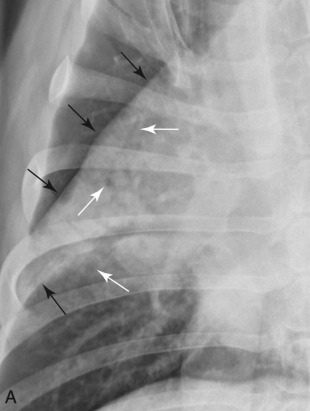

Bronchial signs

Tram line

Doughnuts

기관지벽 두꺼워질 때 보이는 sign

폐 말단으로 갈수록 깨끗한 게 정상

말단에도 tram line 보이면 비정상

VS.

(왼쪽이 정상, 말단으로 갈수록 깨끗. 말단에도 tram line 보이는 오른쪽은 비정상.)

흰색: doughnuts, 검은색: trams)

기관지가 엄청 넓을 때 bronchiectasis